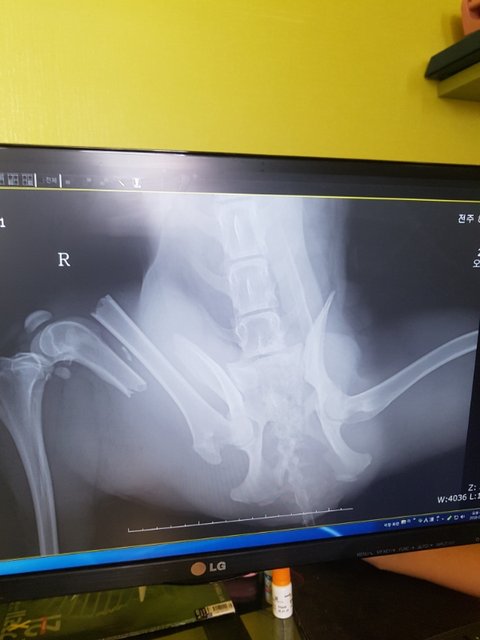

역시나 다발성 골절..

골반뼈와 오른쪽 뒷다리가 부러져 있었습니다